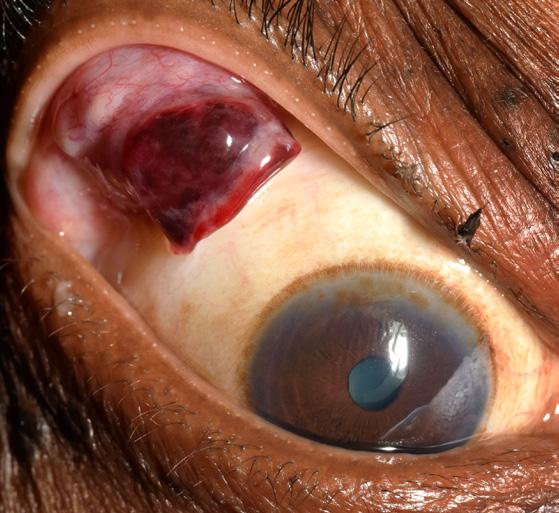

External Photography Hemorrhagic Lid Mass

David Miller, CRA